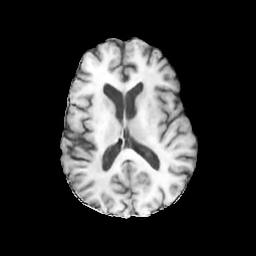

The results presented in Table 1 and 2 show our proposed method’s performance on unconditional 3D brain MR and chest CT image generation. Our proposed approach not only outperforms most comparing methods in FID and MS-SSIM metrics, it also has the lowest inference GPU memory footprint at a resolution of and was the only diffusion-based method that could be trained at a resolution of . Operating in the wavelet domain and profiting from the reduced spatial dimension also results in a relatively short inference time of / at the respective resolutions. Compared to the results presented in [23], we did not find that incorporating wavelet information into the network’s feature space (WavU-Net) increased the model’s performance. Qualitative results of our proposed method (WDM) are shown in Fig. 2 and 3. A qualitative comparison of samples produced by all evaluated methods can be found in the Supplementary Material.